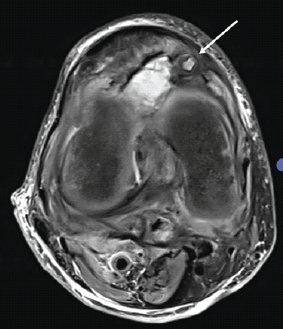

Pseudoaneurysm of the Medial Genicular Artery as a Rare Cause of Recurrent Knee Swelling – A Case Report

Ajayakumar Thankappan , Nizaj Nasimudeen , Ramjith Sivanandan , Jimmy Joseph Meleppuram , Kumar Muthukumar , Prince Shanavas Khan

………………………………p.210-215